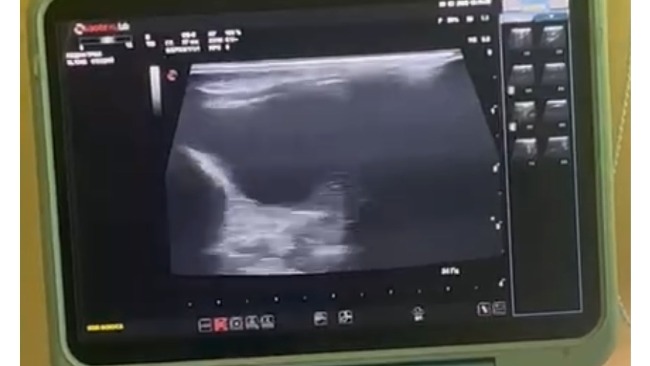

Patrick ma duży brzuszek, było podejrzenie FIP, dziś kociak miał wykonane badanie USG jamy brzusznej. Na szczęście nie ma płynu, ale jelita nie pracują dobrze, przepisano enzymy i leki poprawiające trawienie